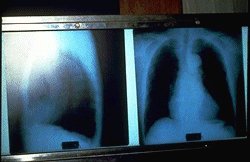

Slide No.10  これは直腸がんで亡くなった仲間のレントゲン写真です。このレントゲン写真から石綿の影響は読み取れませんでした。

本人の遺志と家族の申し出を受け、千葉大学の海老原先生が解剖しました。